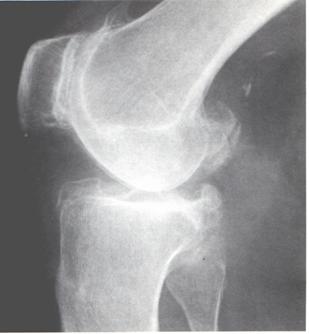

Osteocondrite dissecante (m. di Konig)

Si tratta di una necrosi parcellare che interessa solo una piccola parte, lenticolare, della cartilagine articolare e della corrispondente spongiosa subcondrale dell’epifisi distale del femore o dell’omero.

Compare in età giovanile, in individui robusti, in ginocchia molto sollecitate.

|

Il frammento osseo, in preda a fenomeni necrotici, si demarca nettamente dal tessuto osteocartilagìneo circostante fino a distaccarsi e cadere libero. nell’articolazione (“topo” articolare).

La sintomatologia nella fase prodromica è intermittente, il dolore è scarsamente localizzato, coesistono idrartri recidivanti ed ipotrofia del quadricipite.

Nella fase successiva, quando cioè si è verificato il distacco del cosiddetto “topo” articolare, possono osservarsi fenomeni di blocco dell’articolazione, con impossibilità — se si tratta del ginocchio — a flettere ed estendere la gamba